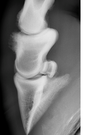

Wat zie je ?

rechts vernauwing gewrichtsinterlinie kogel

teken van isteoartrose